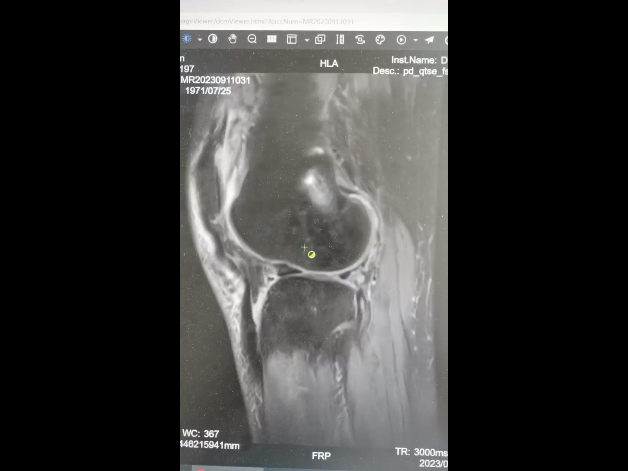

通过查体及辅助膝关节磁共振检查,明确诊断“右膝关节前交叉韧带断裂,外侧半月板撕裂”。